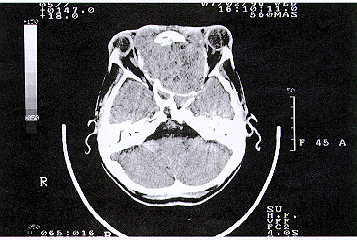

A TC mostrou um tumor extenso, envolvendo ambos os seios maxilares etmóide e esfenóide, com extensão para fossa craniana anterior . Ambos olhos estavam deslocados lateralmente (Fig. 2).

FIGURA 2: T.C. axial revela o tumor envolvendo o seio esfenoidal, etmoidal e os olhos sendo deslocados lateralmente